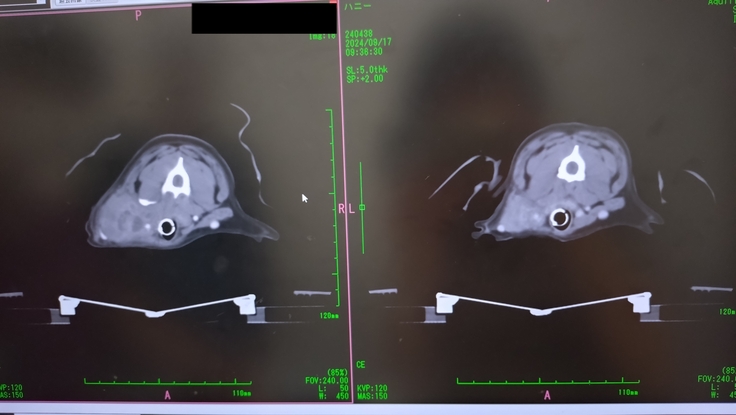

9月17日放射線4回目

9月17日4回目の放射線治療

この日はまたCTを撮り、扁桃腺とリンパ節に4回目の放射線の照射をした。

CTで、扁桃腺とリンパ節に転移した腫瘍はかなり小さくなったのが分かったけど、右前足の付け根の骨に転移が見つかってしまいました😭

この日は既に、扁桃腺とリンパ節への放射線照射は終わっていたので、午後の予約の合間で骨転移の部分の放射線照射もやっていただけることになった。全身麻酔を1日で2回もすることになりそれも心配だった。

先生からは、骨転移があるということは、全身にも回っている可能性が高い。そうなるといたちごっこでどこまで放射線をやってあげるかだと。骨転移し、状況が変わったので、今回、骨転移部分は腫瘍を小さくする目的ではなく、痛みを取るための緩和的照射のみをやりますと。今後は、痛みが治まらなかったり、痛みが出てきた所に緩和的照射を行っていきましょうと。